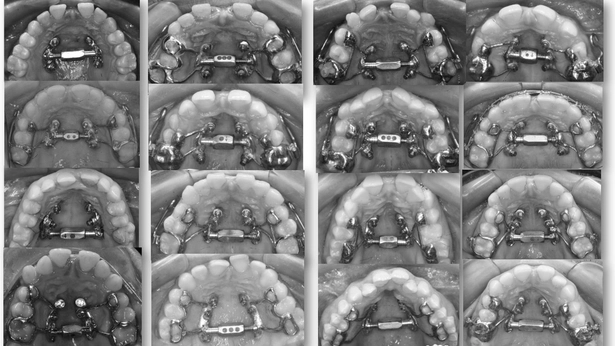

Anclaje esquelético MARPE guiado.

2. E EJECUCIÓN/EQUILIBRIO: Entre la ciencia y la sensibilidad. El ortodoncista moderno vive entre dos mundos: la tradición analógica y la revolución digital. Esta llave enseña a integrarlos. Ni rechazo tecnológico, ni dependencia ciega. EQUILIBRIO es criterio: usar lo nuevo sin olvidar lo esencial. “Lo digital no sustituye al criterio; lo amplifica cuando el juicio clínico está formado.”

3. XCROSS/EXPANSIÓN: La tercera llave es la integración. Cuando biomecánica, cirugía y tecnología se alinean, los límites desaparecen, se amplian las fronteras. Ni la edad ni la complejidad son barreras cuando hay protocolo guiado. Lo que antes era imposible, hoy se resuelve con confianza.

4. I INDEPENDENCIA/INTEGRACIÓN DIGITAL: Precisión con propósito. La tecnología solo tiene valor si mejora la eficiencia clínica. Aquí se aprende a planificar con MARPE, diseñar guías quirúrgicas 3D, optimizar alineadores in-office y flujos híbridos. El objetivo: que cada herramienta digital sirva para mejorar la eficiencia, no simplemente al marketing. “El futuro no está en más software, sino en el uso inteligente del que ya existe.”